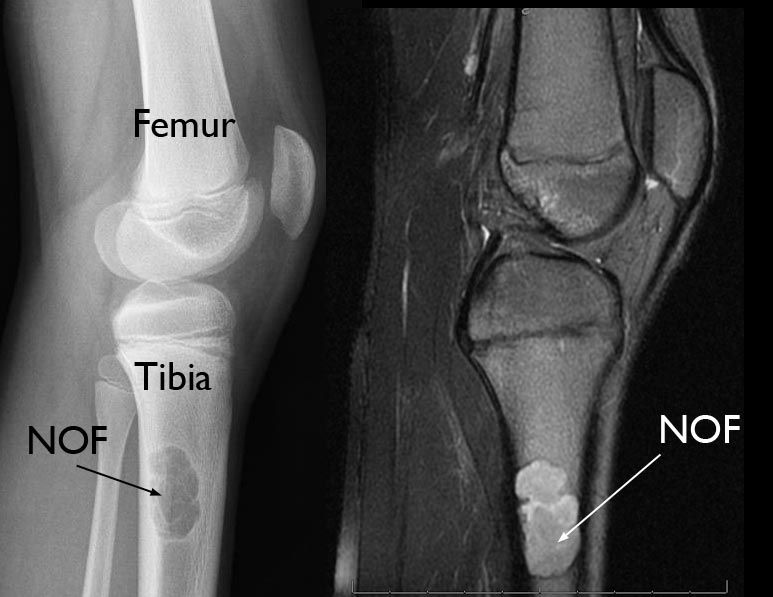

x-ray and mri of nonossifying fibroma

(Left) This X-ray, taken from the side, shows an NOF located in the upper tibia (shinbone). (Right) An MRI scan of the same NOF.

Other imaging tests. In certain cases, a computerized tomography (CT) scan or magnetic resonance imaging (MRI) scan may be needed to further evaluate the tumor.

Although not always necessary, a CT or MRI scan can show the exact size of the tumor, as well as any change in its appearance over time. These images can also show cortical integrity (how thin the strong outer portion of the bone is in the region of the NOF) or a pathologic fracture.